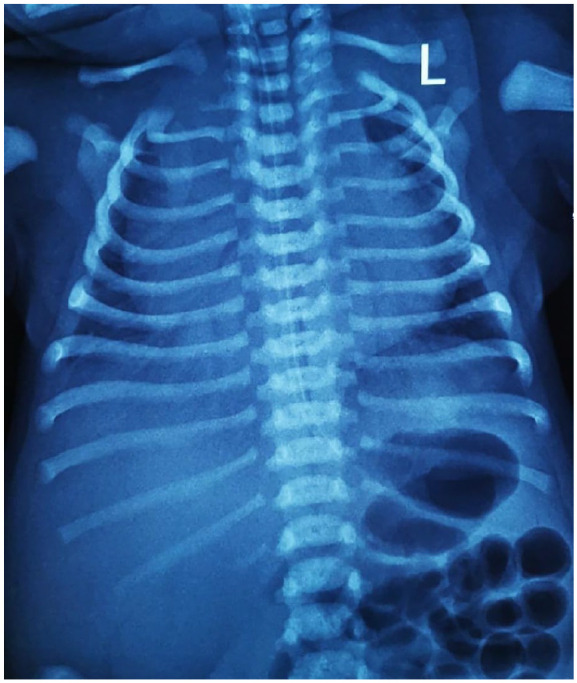

We report a case of a neonate, delivered by C-section, that rapidly developed respiratory compromise and hemodynamic instability prompting admission to critical care. Urgent cardiology assessment with echocardiography revealed severe systolic dysfunction from localized myocardial ischemia and pulmonary hypertension. Their management progressively escalated, eventually requiring inotropic support. Despite intensive treatment and meticulous nursing with demonstrable improvement of cardiac function, they deteriorated suddenly and died on Day 2 post-partum. This case emphasizes the challenge in early recognition of neonatal shock due to often nonspecific presentations, with hemodynamic compromise arising later. We recommend close vigilance for deterioration, awareness of indolent etiology including viral myocarditis, titration of appropriate inotropes and synergistic adjunctive vasodilators, and consideration of immune modulators such as corticosteroids that addresses biochemical deficiencies and support cardiac function. Ultimately, aggressive, targeted, and multi-focal treatment, especially in resource-limited environments, maximizes the chances of survival in challenging clinical situations such as progressive neonatal shock.